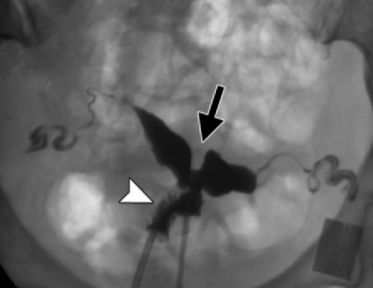

Uterus Septé

Bicorne VS Septé